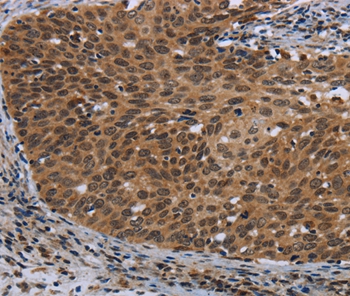

Immunohistochemical analysis of paraffin-embedded Human cervical cancer tissue using #36790 at dilution 1/40.

Immunohistochemistry: 1:50-1:200